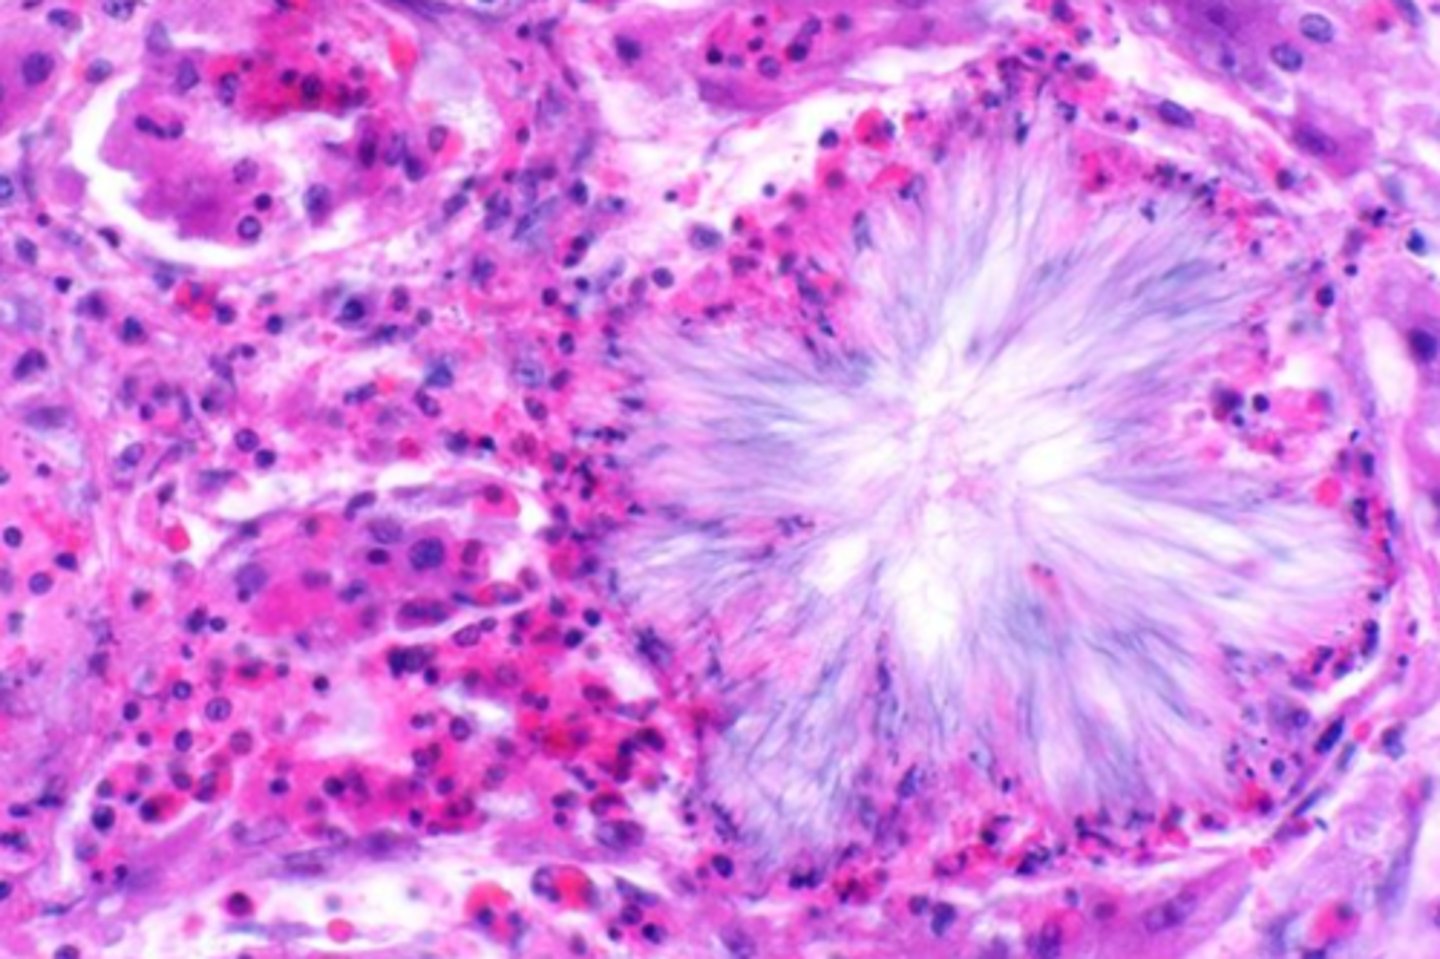

cholesterol

_______________ crystals can form at sites of hemorrhage or necrosis but dissolve during processing, forming acicular clefts seen in histologic sections

macrophages

what do cholesterol crystals attract?

what is this extracellular inclusion?

<p>what is this extracellular inclusion?</p>